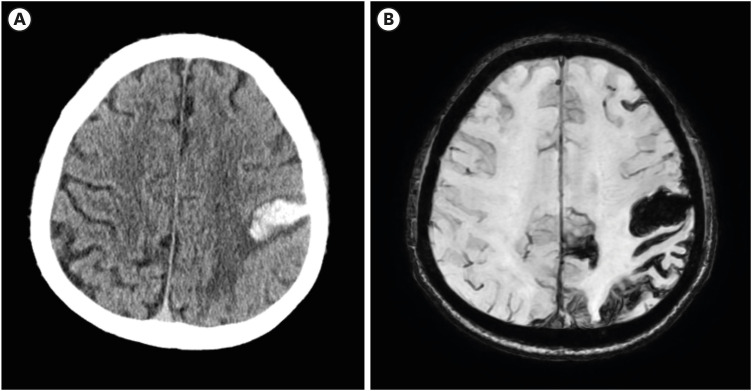

Intracerebral hemorrhage (ICH) is the second most common stroke subtype associated with high morbidity and mortality rates. Although various brain regions are susceptible to ICH, putaminal hemorrhage is the most common, whereas cortical ICH is less common. Here, we report the case of a 69-year-old man who developed a parietal cortical ICH. The patient developed hypoesthesia and paresthesia in the right upper lip and hand; however, the weakness was not severe. Twenty-five days after the ICH onset, the manual muscle test results were normal, but he had difficulty eating and shaving because of decreased hand dexterity. The rehabilitation focused on improving fine hand motor function and endurance. On the 94th day after ICH onset, paresthesia remained only in the fingertips, and the upper lip sensory change disappeared. Patients with sensory symptoms in the perioral area, hands, and brain lesions were previously referred to as having cheiro-oral syndrome (COS). With the advancement of neuroimaging, the use of this term has decreased, as cerebrovascular events can explain patient symptoms in correlation with neuroanatomy, etiology, and pathogenesis. We report a patient with cortical ICH, also known as COS, which is a stroke syndrome with a good prognosis.